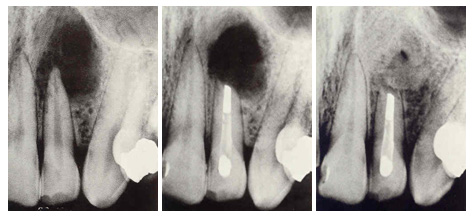

Sıcak ve soğuğa karşı uzun süreli hassasiyet Çiğnerken oluşan ağrı ya da rahat çiğneyememe Kendi ...

Her dişin ortasından onun beslenmesini ve duyarlılığını sağlayan damar ve sinir paketi geçer. Bu dam ...